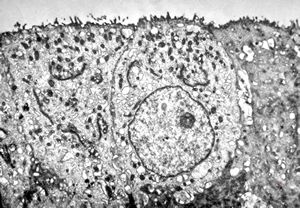

M,3m. | type II. pneumocyte